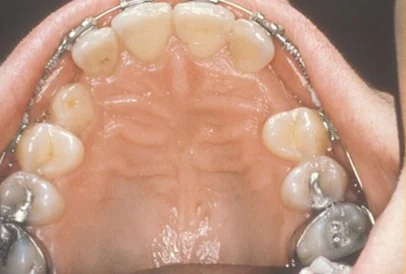

Normally, the maxillary cuspid teeth are the last of the “front” teeth to erupt into place. They usually come into place around age 13 and cause any space left between the upper front teeth to close tighter together. If a cuspid tooth gets impacted, every effort is made to get it to erupt into its proper position. The techniques involved to aid eruption can be applied to any impacted tooth in the upper or lower jaw, but most commonly they are applied to the maxillary cuspid (upper eye) teeth. Sixty percent of these impacted eyeteeth are located on the palatal (roof of the mouth) side of the dental arch. The remaining impacted eye teeth are found in the middle of the supporting bone, but are stuck in an elevated position above the roots of the adjacent teeth, or are out to the facial side of the dental arch.